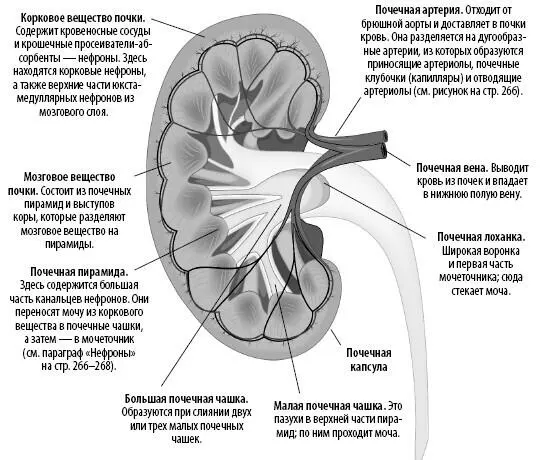

Если разрезать почку пополам во фронтальной плоскости, то можно увидеть, что она состоит из нескольких разных структур.

Наши почки частично прикрыты нижними ребрами. Правая почка немного меньше левой и находится чуть ниже, поскольку над ней расположена печень. Каждая почка покрыта тонкой почечной капсулой, состоящей из фиброзной соединительной ткани. Даже с одной здоровой почкой человек может жить, хотя это и рисковано: вторая почка служит резервом или заменой первой, если по каким-то причинам та не сможет выполнять свою функцию.

На этой компьютерной томограмме видны корковый и мозговой слои, почечные чашки, ворота почки, центральная часть почки с впадающими/выходящими кровеносными сосудами, нервами и мочеточник.

Каждая почка содержит около миллиона крошечных структур под названием «нефроны». Сами нефроны состоят из двух частей: почечного тельца и канальца. По своему расположению нефроны делятся на корковые (кортикальные) и юкстамедуллярные.

Фильтрация происходит в сферических структурах, называемых почечными тельцами. В них содержится капиллярная сеть — почечные клубочки, которые выходят из приносящих (афферентных) артериол и сворачиваются в чашеобразную структуру — Боуменову капсулу. В почечном тельце создается огромное давление, из-за которого вода и растворенные в крови продукты жизнедеятельности отфильтровываются капиллярами через специальные поры и попадают в Боуменову капсулу — начало почечного канальца.

Нефрон является основной структурно-функциональной единицей почки и образует ее тканевый каркас.

Почечные клубочки

Эти капиллярные узлы формируют первичный капиллярный слой нефрона (всего их два). Клубочки образуют фильтрующую поверхность с площадью свыше 500 кв. см. Капиллярные стенки клубочков формируют подобие сита, которое пропускает небольшие молекулы (воду, соли, гормоны, глюкозу и водорастворимые витамины) в Боуменову капсулу и блокирует крупные молекулы (белки плазмы (альбумин) и клетки крови). Процеженная кровь выходит из клубочков через отводящие (эфферентные) артериолы, которые разветвляются на вторичное капиллярное русло, околоканальцевые капилляры и прямые сосуды. Далее кровь проходит по петле Генле и попадает в венозную систему.

Собирательные протоки не являются частью нефрона; они собирают фильтрат из нескольких нефронов и определяют концентрацию мочи. Регулирует этот процесс гипофизарный антидиуретический гормон (АДГ), который увеличивает проницаемость стенок для воды и позволяет большему ее количеству реабсорбироваться в кровь. Этим и объясняется тот факт, что наша моча по утрам более концентрирована: в ночное время выделяется больше АДГ. Фильтрат (а теперь это уже моча) перетекает из собирательных протоков в почечные чашки, затем в почечную лоханку и выводится в мочеточник.